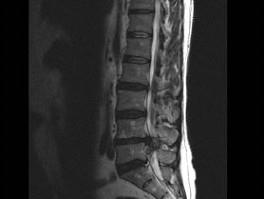

男,52岁,“坐骨神经痛”3个月余,请结合影像学检查,选出最可能的诊断 ( )A、椎间盘突出B、神经根鞘囊肿C、椎间盘炎D、硬...

相关内容:坐骨神经痛,月余,影像学,检查,选出,可能,诊断,椎间盘,神经,根鞘,囊肿